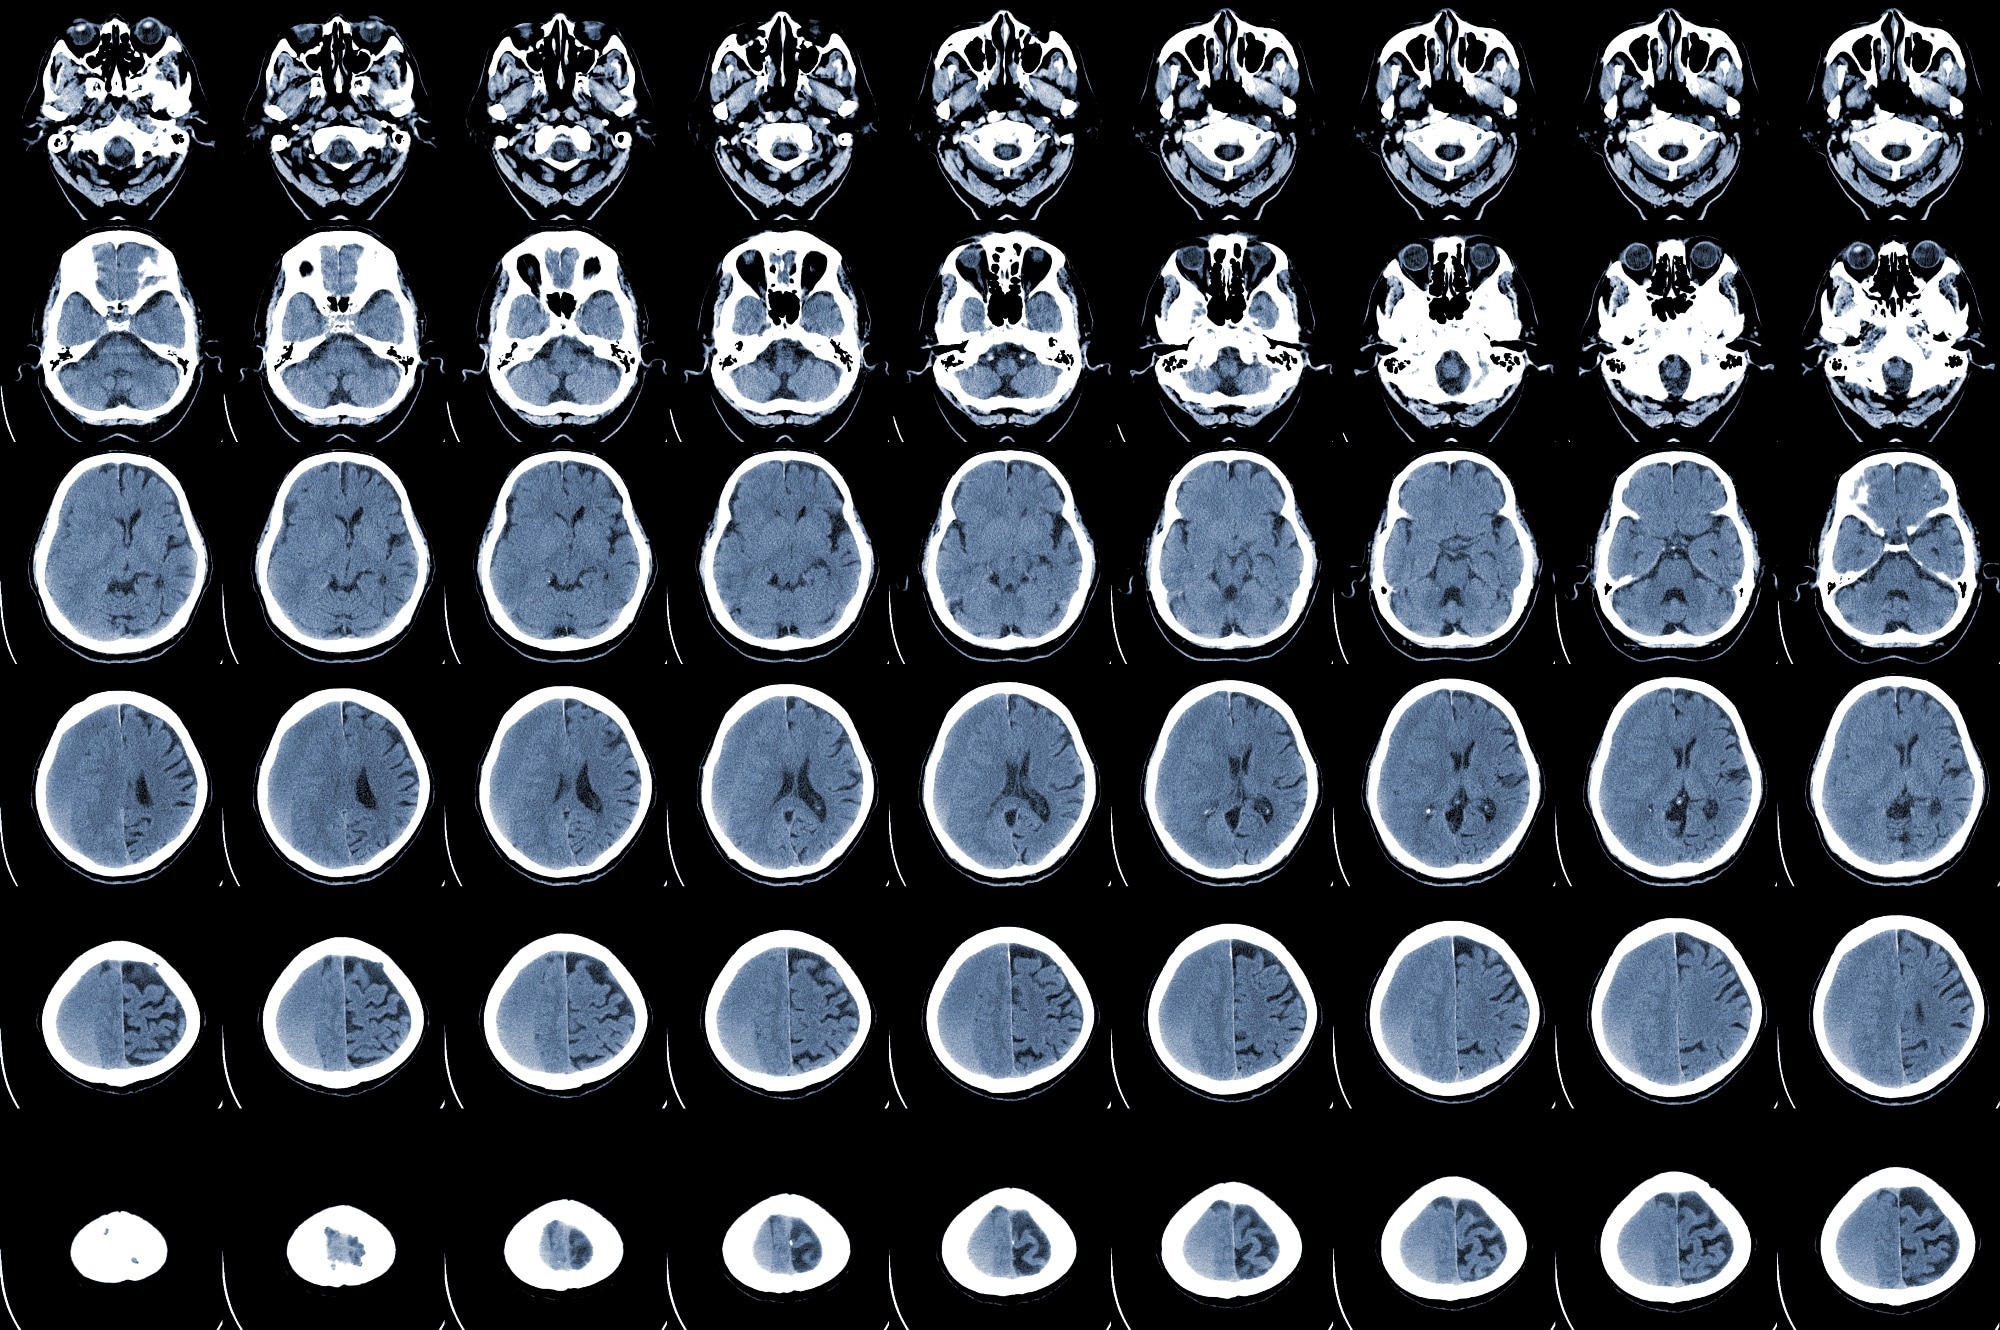

Study: The impact of SARS-CoV-2 infection on the outcome of acute ischemic stroke—A retrospective cohort study. Image Credit: April stock / ShutterstockStudy: The impact of SARS-CoV-2 infection on the outcome of acute ischemic stroke—A retrospective cohort study. Image Credit: April stock / Shutterstock

All AIS patients considered in this study exhibited acute neurologic signs of stroke and ischemia, confirmed using Magnetic Resonance Imaging (MRI) and Computed Tomography (CT) of the head. For this study, the authors collected relevant demographic data, medical history, stroke characteristics, length of hospitalization, in-hospital mortality, the number of patients transferred to an intensive care unit (ICU) facility, and laboratory test reports.

Imaging data revealed that multiple vessel territorial involvement was similar in both COVID-19 AIS and non-COVID-19 AIS groups. A higher large vessel occlusion rate was found in the COVID-19 group, with larger anterior circulation LVO in the COVID-19 AIS group. Notably, in the COVID-19 AIS group, patients with pneumonia mainly exhibited higher LVO prevalence, which indicated a stronger association between COVID-19 pneumonia and LVO. In the future, more research is required to validate this finding.